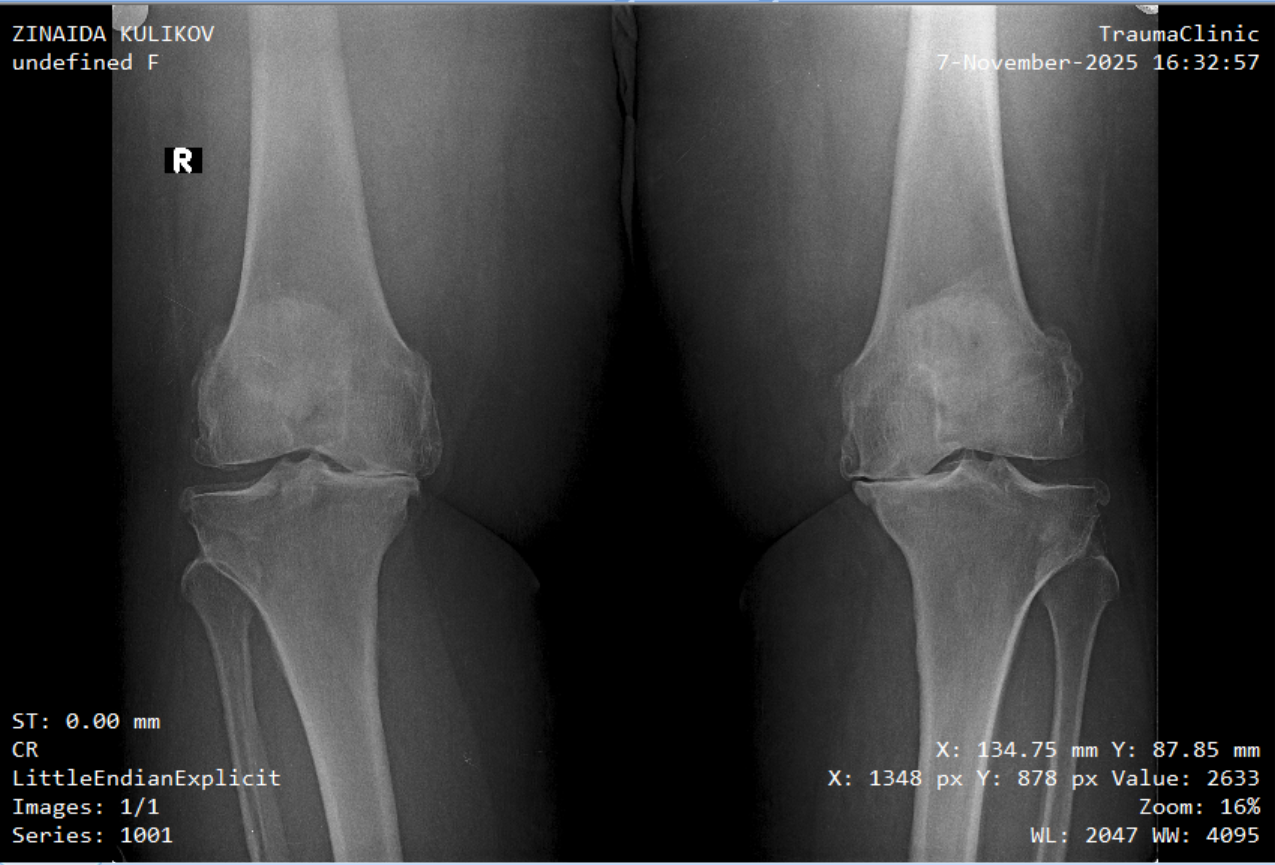

Zina has been battling severe knee arthritis for over 15 years. Despite the pain, she’s carried on with remarkable strength. But recently, things have worsened. She’s been diagnosed with stage 4 arthritis—her joints are severely damaged, and there’s no cartilage left. Her bones grind painfully with every step. Her doctor was amazed she could still walk without support.

After five years of waiting and planning, Zina finally underwent knee replacement surgery here in Santa Cruz, Bolivia. She’s currently recovering in the hospital, and we’re hopeful this marks the beginning of a new chapter—one without constant pain.